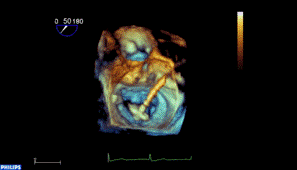

Avaliação Ecocardiográfica de Insuficiência Mitral

Avaliação Ecocardiográfica de Insuficiência Mitral Severa

Mitra Clip - Step by Step Sala de Hemodinâmica